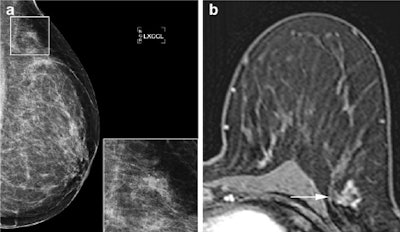

At pathology, 40 of 123 (33%) lesions proved malignant, and 70% of those were DCIS, the rest were invasive carcinoma. The two observers detected all invasive malignancies at MRI, as well as 79% (observer 1) and 86% (observer 2) of in situ lesions. MRI in addition to conventional imaging led to a significant increase in area under the receiver operating characteristic (ROC) curve from 0.67 to 0.79 for observer 1 and to 0.80 for observer 2.

However, only low- and intermediate-grade DCIS are affected in this instance and not high-grade DCIS or invasive carcinomas -- in fact, almost all the DCIS lesions detected on MRI were high-grade in the study.

"In the end, DCIS is regarded as a potential precursor lesion of invasive disease, and is therefore treated with breast-conserving therapy followed by radiation therapy," they wrote. "Our results do show an added diagnostic value of 3T breast MRI to conventional imaging, but unfortunately MRI does not exclude DCIS lesions of all grades sufficiently in all cases, and its sensitivity is not high enough to replace biopsy."